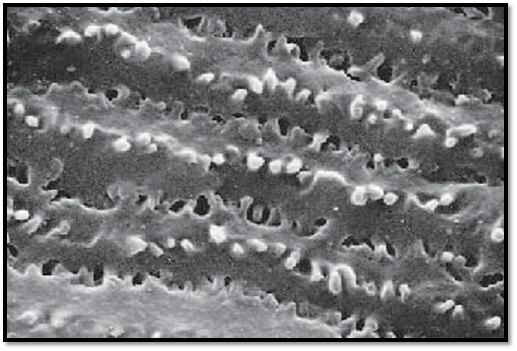

Eye and Lens

The lens consists of lens capsule ( capsula lentis), the lens epithelium ( epithelium lentis), subcapsular epithelium and the lens fibers ( fibrae lentis ). The lens fibers arise from the lens epithelium . Lens fibers are thin cells, 7–10 μm long and about 2- μm thick , containing crystallin. The cells lose their nuclei during development. They form long bands that appear hexagonal in cross-sections. The bands consist of concentric layers of radial lamellae. The lamellae are connected via focal desmosomes (junctional complexes). Interdigitations are present at the corner structures of the hexagonal lamellae. Note the focal desmosomes between intercellular processes. There are about 2300 lamellae in the adult human.

Scanning electron microscopy; magnification: × 4000

Kuehnel, W.(2003). Color Atlas of Cytology, Histology, and Microscopic Anatomy. 4th edition . Institute of Anatomy Universitätzu Luebeck Luebeck, Germany . Thieme Stuttgart · New York .